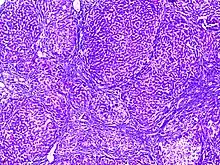

![]() | Dysgerminoma | Dysgerminoma characterized by uniform cells resembling primordial germ cells separated by fibrous septa with lymphocytes. | Category: Histopathology of ovarian dysgerminoma | Ovarian dysgerminoma |